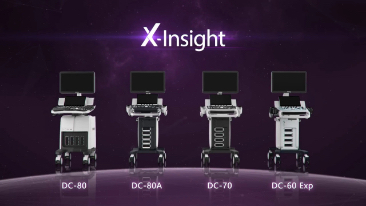

DC-60 Exp

X-Insight ├© una soluzione completa studiata per offrire la migliore qualit├Ā diagnostica.

La nuova soluzione di Mindray ├© la traduzione pratica delle esigenze quotidiane dei clienti in soluzioni cliniche, il tutto con tecnologie ad ultrasuoni all'avanguardia ed in continua evoluzione.

Proponendosi come partner affidabile, DC-60 Exp con X-Insight si concentra su ci├▓ che conta veramente, semplificando la gestione della pratica clinica quotidiana con facilit├Ā e sicurezza.

Progettato per rispondere al meglio alle esigenze del cliente, DC-60 Exp con X-Insight ├© studiato per offrire un'efficienza elevata nel campo dell'imaging di precisione, grazie a una chiarezza immediata (eXpress Clarity), allŌĆÖeccezionale intelligenza (eXceptional Intelligence), oltre a vantare una lunghissima esperienza (eXceeding Experience).